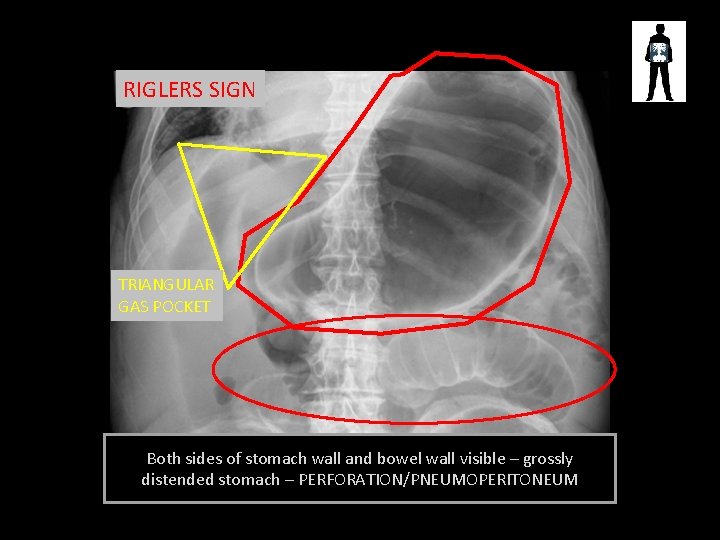

RIGLERS SIGN TRIANGULAR GAS POCKET Both sides of stomach wall and bowel wall visible – grossly distended stomach – PERFORATION/PNEUMOPERITONEUM